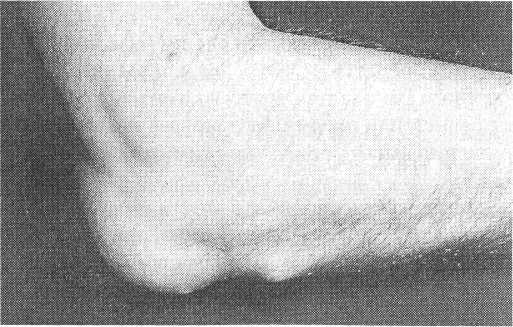

Обычно ревматоидный артрит начинается с симметричного полиартрита периферических суставов (рис.1), что проявляется их припухлостью, болезненностью и скованностью, причем последняя может поражать большее количество суставов, чем первые два симптома. Характерным для ревматоидного артрита является вовлечение проксимальных межфаланговых, пястно-фаланговых суставов и лучезапястных суставов кистей. Дистальные межфаланговые суставы, пястно-фаланговый сустав I пальца и проксимальный межфаланговый сустав V пальца кисти считаются "суставами исключения" так как в большинстве случаев остаются интактными в дебюте болезни, однако могут вовлекаться в процесс при прогрессировании ревматоидного артрита.

Припухлость пястно-фаланговых и проксимальных межфаланговых суставов кисти с веретенообразной де фигурацией последних, ассоциирующаяся с утренней скованностью, затруднением сжатия кисти в кулак, снижением кистевой силы и болезненностью при пальпации (см. рис.1).

Рис.1. Кисты больного с ранним ревматоидным артритом